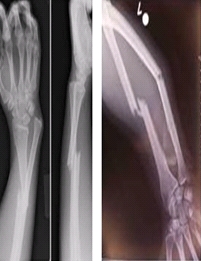

이러한 골다공증이 생기면 뼈가 아프고,

가벼운 충격에도 쉽게 뼈가 부러질 수 있고,

그로 인해 통증이 발생할 수 있습니다.